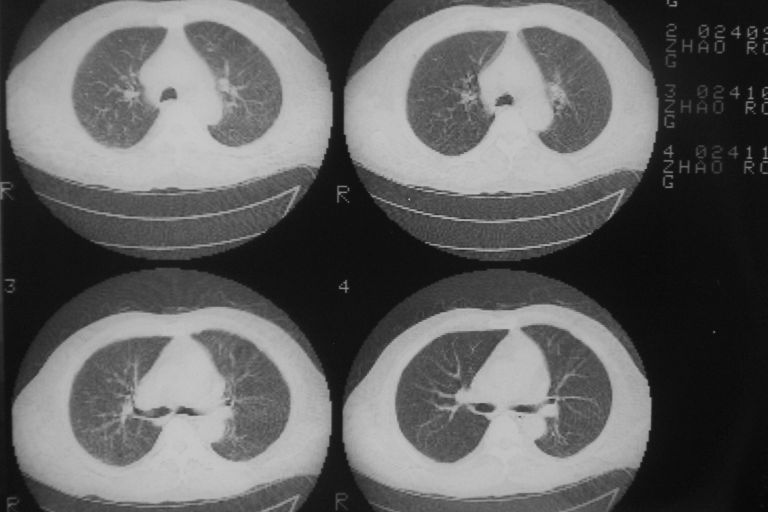

患者 男 50岁 无痛性咯血3天,无其他不适.

左下肺结节状软组织密度影,边缘有毛刺,考虑周围型肺癌。

1 左肺下叶基底段见两结节软组织密度灶, 肺窗边缘见有毛刺征像, 不能排除占位. 2 建议结合临床治疗一周后ct随访在看其结果.

左下肺基底段两个小结节影,边缘毛糙,建议抗炎治疗后复查。

临近胸膜增厚,病变周围肺不清,稍有分叶。结节密度略高,肺、纵隔窗差异不大,肺癌待排。前方还有一个

1 左肺下叶后基底段见结节软组织密度灶,周围见毛刺,建议抗炎后复查,警惕周围型肺癌。

左下肺结节状软组织密度影,一个边缘有卫星病灶,邻近胸膜增厚.另一个有毛刺.心影周围水样密度影环绕.考虑:

1.肺癌可能.肺tb待排.

2.左侧胸膜增厚.心包积液.